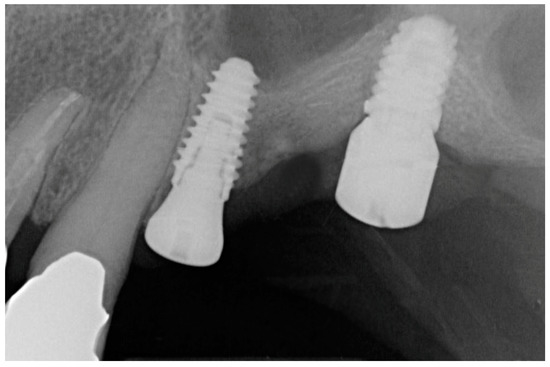

2. Materials and Methods